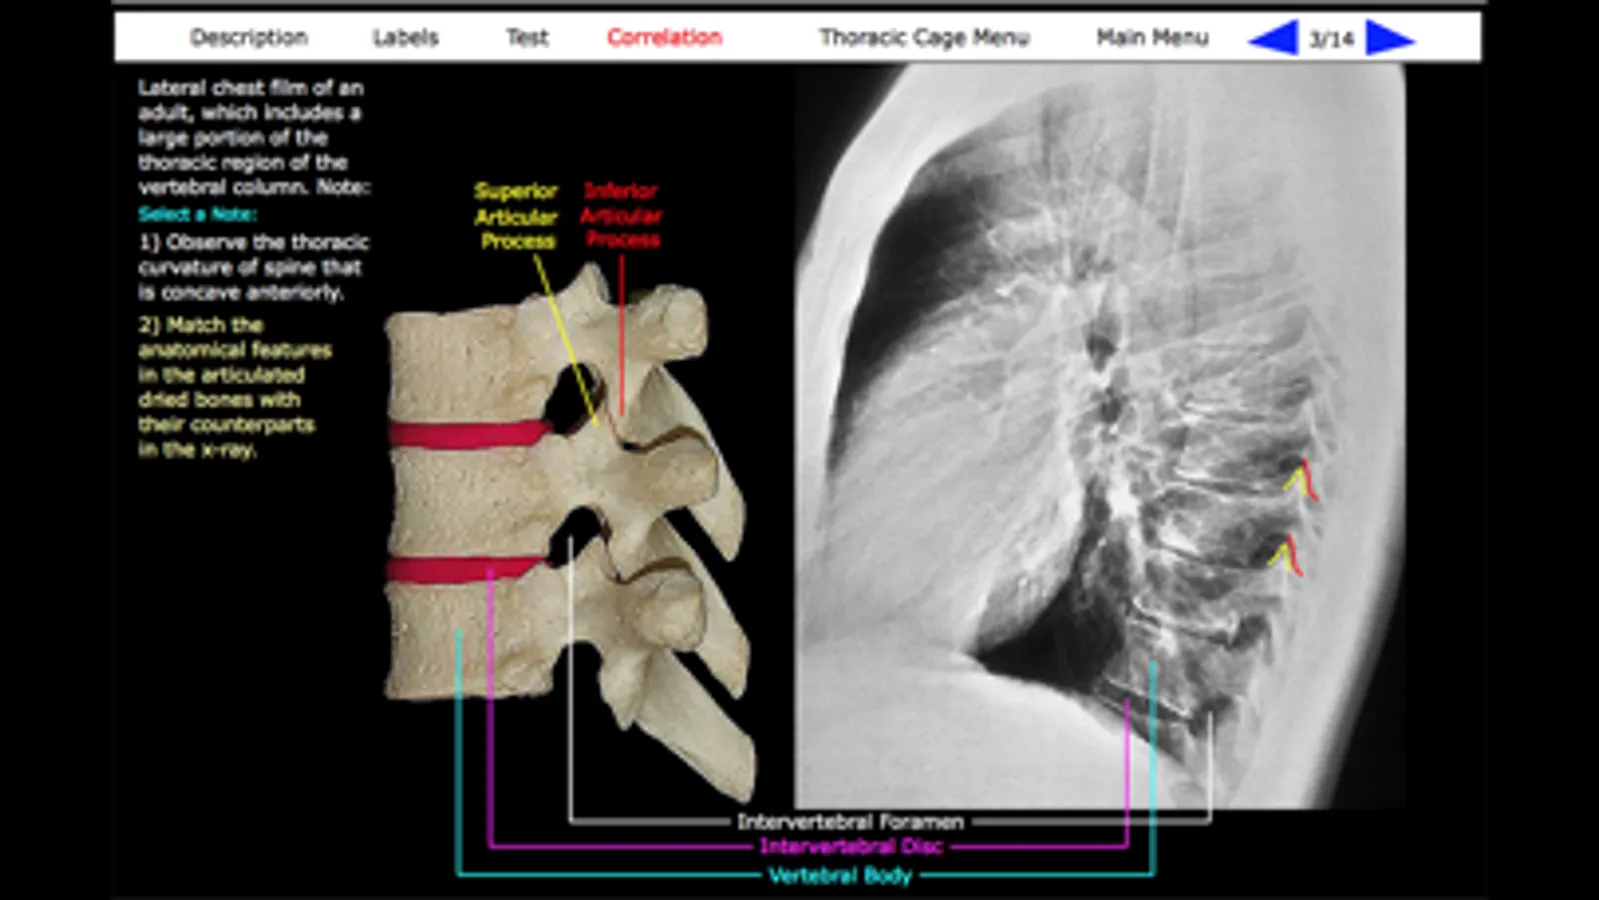

Correlation: Many of the bone images have an accompanying Correlation image. The Correlation image is designed to relate the gross anatomical features of the bone with their appearance in another visual medium, such as an x-ray. This feature is particularly valuable to users with an interest in the clinical sciences.